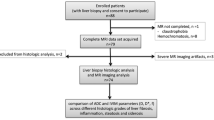

This prospective study was approved by the institutional review board, and informed consent was obtained from all participants. A total of 102 patients with chronic HBV infection were recruited consecutively and underwent liver magnetic resonance (MR) examinations (including routine sequences and DWI with multiple b-values) between June 2014 and December 2016. The inclusion criteria were as follows: (a) MR imaging was performed prior to liver biopsy, and the interval between MR imaging and liver biopsy was less than one month; (b) pathological results were obtained; (c) the patients had no surgical history involving the right lobe of the liver. The exclusion criteria were as follows: (a) MR data were not available due to respiratory artefacts; (b) patients had other focal lesions in the liver. Based on the exclusion and inclusion criteria, 20 patients were excluded from the study for the following reasons: four did not undergo liver biopsy, six had poor images with artefacts, four had other lesions, and six had fatty liver disease. Consequently, a total of 82 patients (55 males and 27 females; mean age: 36.7 years, age range: 22–61 years) were included in this study (Fig. 1). Concomitantly, 30 healthy subjects (8 males and 22 females, mean age: 31.3 years, age range: 22–69 years) with no history of liver disease, alcohol abuse, liver dysfunction, and liver biopsy were enrolled as the control group (Fig. 1). All the healthy subjects had undergone liver MR examinations.

Results

Histological quantification of fibrosis stage and inflammatory activity grade was performed in 82 patients with CHB by liver biopsy. The fibrosis stage distribution is as follows (Fig. 1): F0, n = 1; F1, n = 16; F2, n = 31; F3, n = 19; and F4, n = 15. The inflammatory activity grade distribution is as follows: A0, n = 1; A1, n = 14; A2, n = 46; and A3, n = 21.